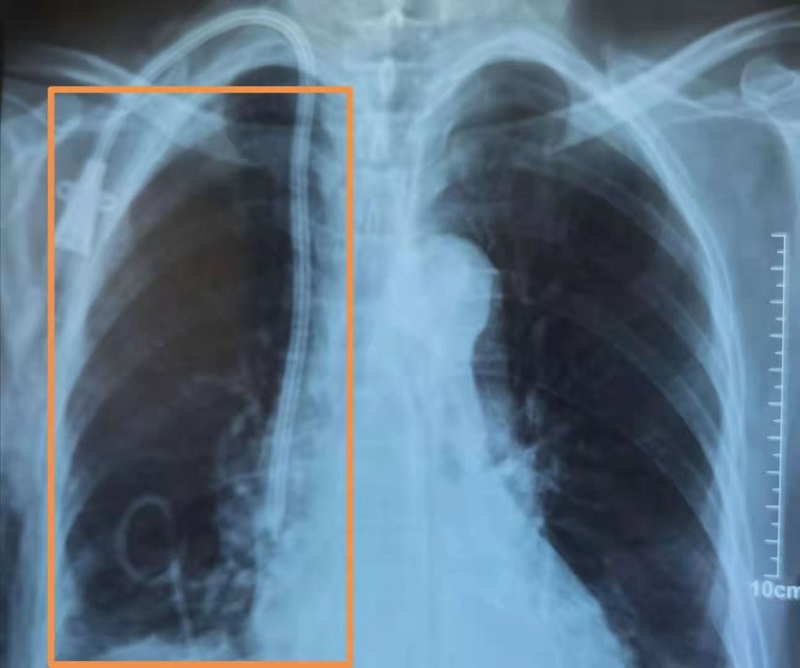

患者女性,68岁,患慢性肾衰竭、尿毒症多年,1月26日入住我院肾病科进行维持性血液透析治疗。入院时,胸闷、气短、身体乏力,并伴有咳嗽、咳痰等症状,胸部CT检查提示右侧液气胸,右肺肺不张(外压型)。本着为病人全程负责的理念,肾病科及时邀请外科会诊,外科建议立即请B超室配合行胸腔穿刺闭式引流术,否则患者将会有生命危险。随后,肾病科和B超室协作,紧急为患者进行了B超引导下穿刺引流,手术过程顺利。

术后患者胸闷、气短、乏力、咳嗽等症状明显好转,1月31日复查胸片,气胸明显改善,右肺复张。2月1日上午拔除闭式引流管后,患者生命体征平稳,趋于好转。